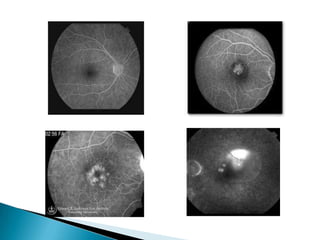

   Dark appearance of the fovea on FFA is

caused by FAZ and blockage of the choroidal

background by xanthophyll and dense RPE

   FFA is a very useful tool in diagnosing

macular disorders e.g. diabetic maculopathy,

CSR , CNVM and can reveals the functionality

of the lesion e.g. ischemic maculopathy

Dark appearance of the fovea on FFA is caused by FAZ and blockage of the choroidal background by xanthophyll and dense RPE  FFA is a very useful tool in diagnosing macular disorders e.g. diabetic maculopathy, CSR , CNVM and can reveals the functionality of the lesion e.g. ischemic maculopathy